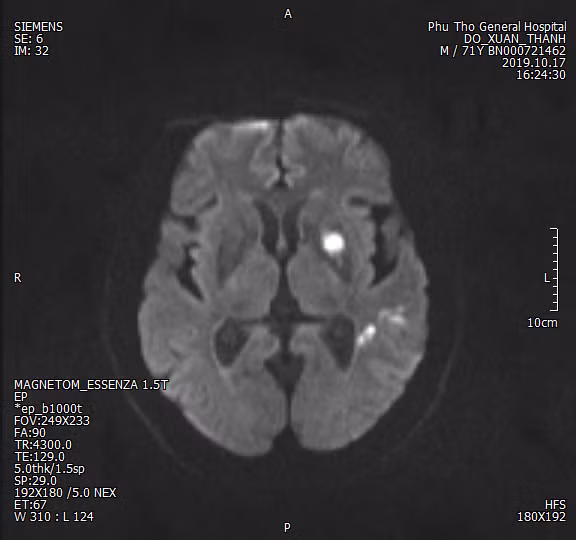

Người bệnh Đ.X.Th là nam giới, 71 tuổi, Cẩm Khê - Phú Thọ, được chuyển tuyến từ Trung tâm Y tế huyện Cẩm Khê trong tình trạng ý thức lơ mơ, liệt nửa người, thất ngôn vận động, liệt mặt, rối loạn nuốt nặng với tiền sử nhồi máu não cách đây 4 tháng không để lại di chứng

Bệnh nhân ngay lập tức được chỉ định sử dụng chụp cắt lớp vi tính có sử dụng trí tuệ nhân tạo (RAPID). Hình ảnh RAPID phát hiện gần như toàn bộ vùng thân não người bệnh bị tổn thương, thể tích vùng cần cứu lên đến 40ml.

Hệ thống mạch sau khi được dựng 3D ở nhiều góc độ giúp các bác sỹ kết luận người bệnh bị tắc động mạch đòi hỏi phải can thiệp sớm để lấy huyết khối và tái thông mạch.